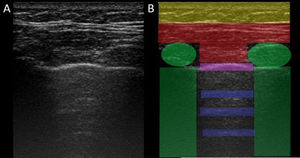

El USP se realiza a través de los espacios intercostales con la sonda perpendicular a la superficie torácica en posición longitudinal, apoyando sus extremos proximal y caudal sobre las costillas superior e inferior que delimitan el espacio intercostal. Las referencias óseas son las crestas óseas costales. La pleura visceral y parietal se representan como una sola línea ubicada 0,5cm por debajo de las crestas costales, llamada «línea pleural». La apariencia de las 2 imágenes costales con la línea pleural intermedia se conoce como el «signo del murciélago» (fig. 1).

Imagen de ultrasonido normal realizado en paciente sano, obtenida con equipo GE Logiq 3 con transductor lineal multifrecuencia de 10-14MHz, en el tercer espacio intercostal derecho, con paciente en posición decúbito supino y transductor en orientación longitudinal. A) Imagen original. B) Resaltado en amarillo piel y tejido celular subcutáneo; en rojo, capas miofasciales; en verde, costillas y la sombra acústica qgenran; en morado, línea pleural, y en azul, líneas A.

En el pulmón normal, debido a la gran diferencia de impedancia acústica entre el aire y los tejidos blandos circundantes, la pleura se comporta como reflector casi perfecto de las ondas de ultrasonido; produce múltiples fenómenos de reverberación entre la línea pleural y la sonda. La línea pleural se visualiza hiperecoica, brillante, delgada y regular, con movimiento deslizante suave y sincrónico con la respiración llamado «deslizamiento pulmonar». Debajo de la línea pleural hay artefactos horizontales característicos: «líneas A», que son réplicas de la línea pleural dispuestas de forma equidistante entre sí debido a la reverberación del ultrasonido en la línea pleural y artefactos resultantes de las capas miofasciales de la pared torácica debido a fenómenos de reverberación menores y efectos de espejo24.